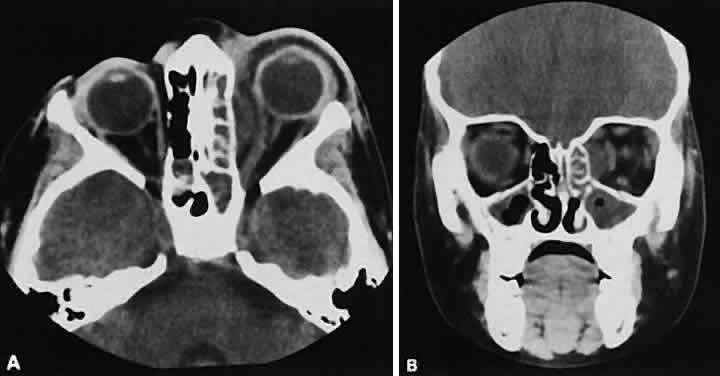

Nonspecific inflammatory dacryoadenitis shows enlargement of the lacrimal gland, which typically molds to the shape of the globe (Fig. 6). The adjacent bone is normal, and contrast enhancement of the gland usually is fairly homogeneous. Bilateral involvement may be apparent with certain conditions such as Sjogren's syndrome, sarcoidosis, lymphoma, or even Graves' orbitopathy, although enlarged EOM in the latter condition might make this a more obvious diagnosis.

Fig. 6. Nonspecific inflammatory dacryoadenitis. An isodense enlargement of the lacrimal gland is noted on axial (A) and coronal (B) views. Note the similarity to Figure 18.

Lymphomatous involvement of the lacrimal gland resembles inflammatory dacryoadenitis radiographically. The enlarged lacrimal gland conforms to the shape of the globe, and the adjacent bone is normal (Fig. 18). We are aware of three high-grade lymphomas that affected the orbit and lacrimal gland and indented the globe, but this is distinctly unusual. Non-Hodgkin's B-cell lymphomas represent the most common type of lymphoma to affect the orbit. Literally any structure in the orbit can be subject to lymphomatous involvement; therefore, a lymphoma should be suspected in the presence of any amorphous isointense infiltrative process.

Fig. 18. Axial (A) and coronal (B) views of lacrimal gland lymphoma. There is homogenous enhancement of the enlarged lacrimal gland. Compared with Fig. 6, there is no difference.